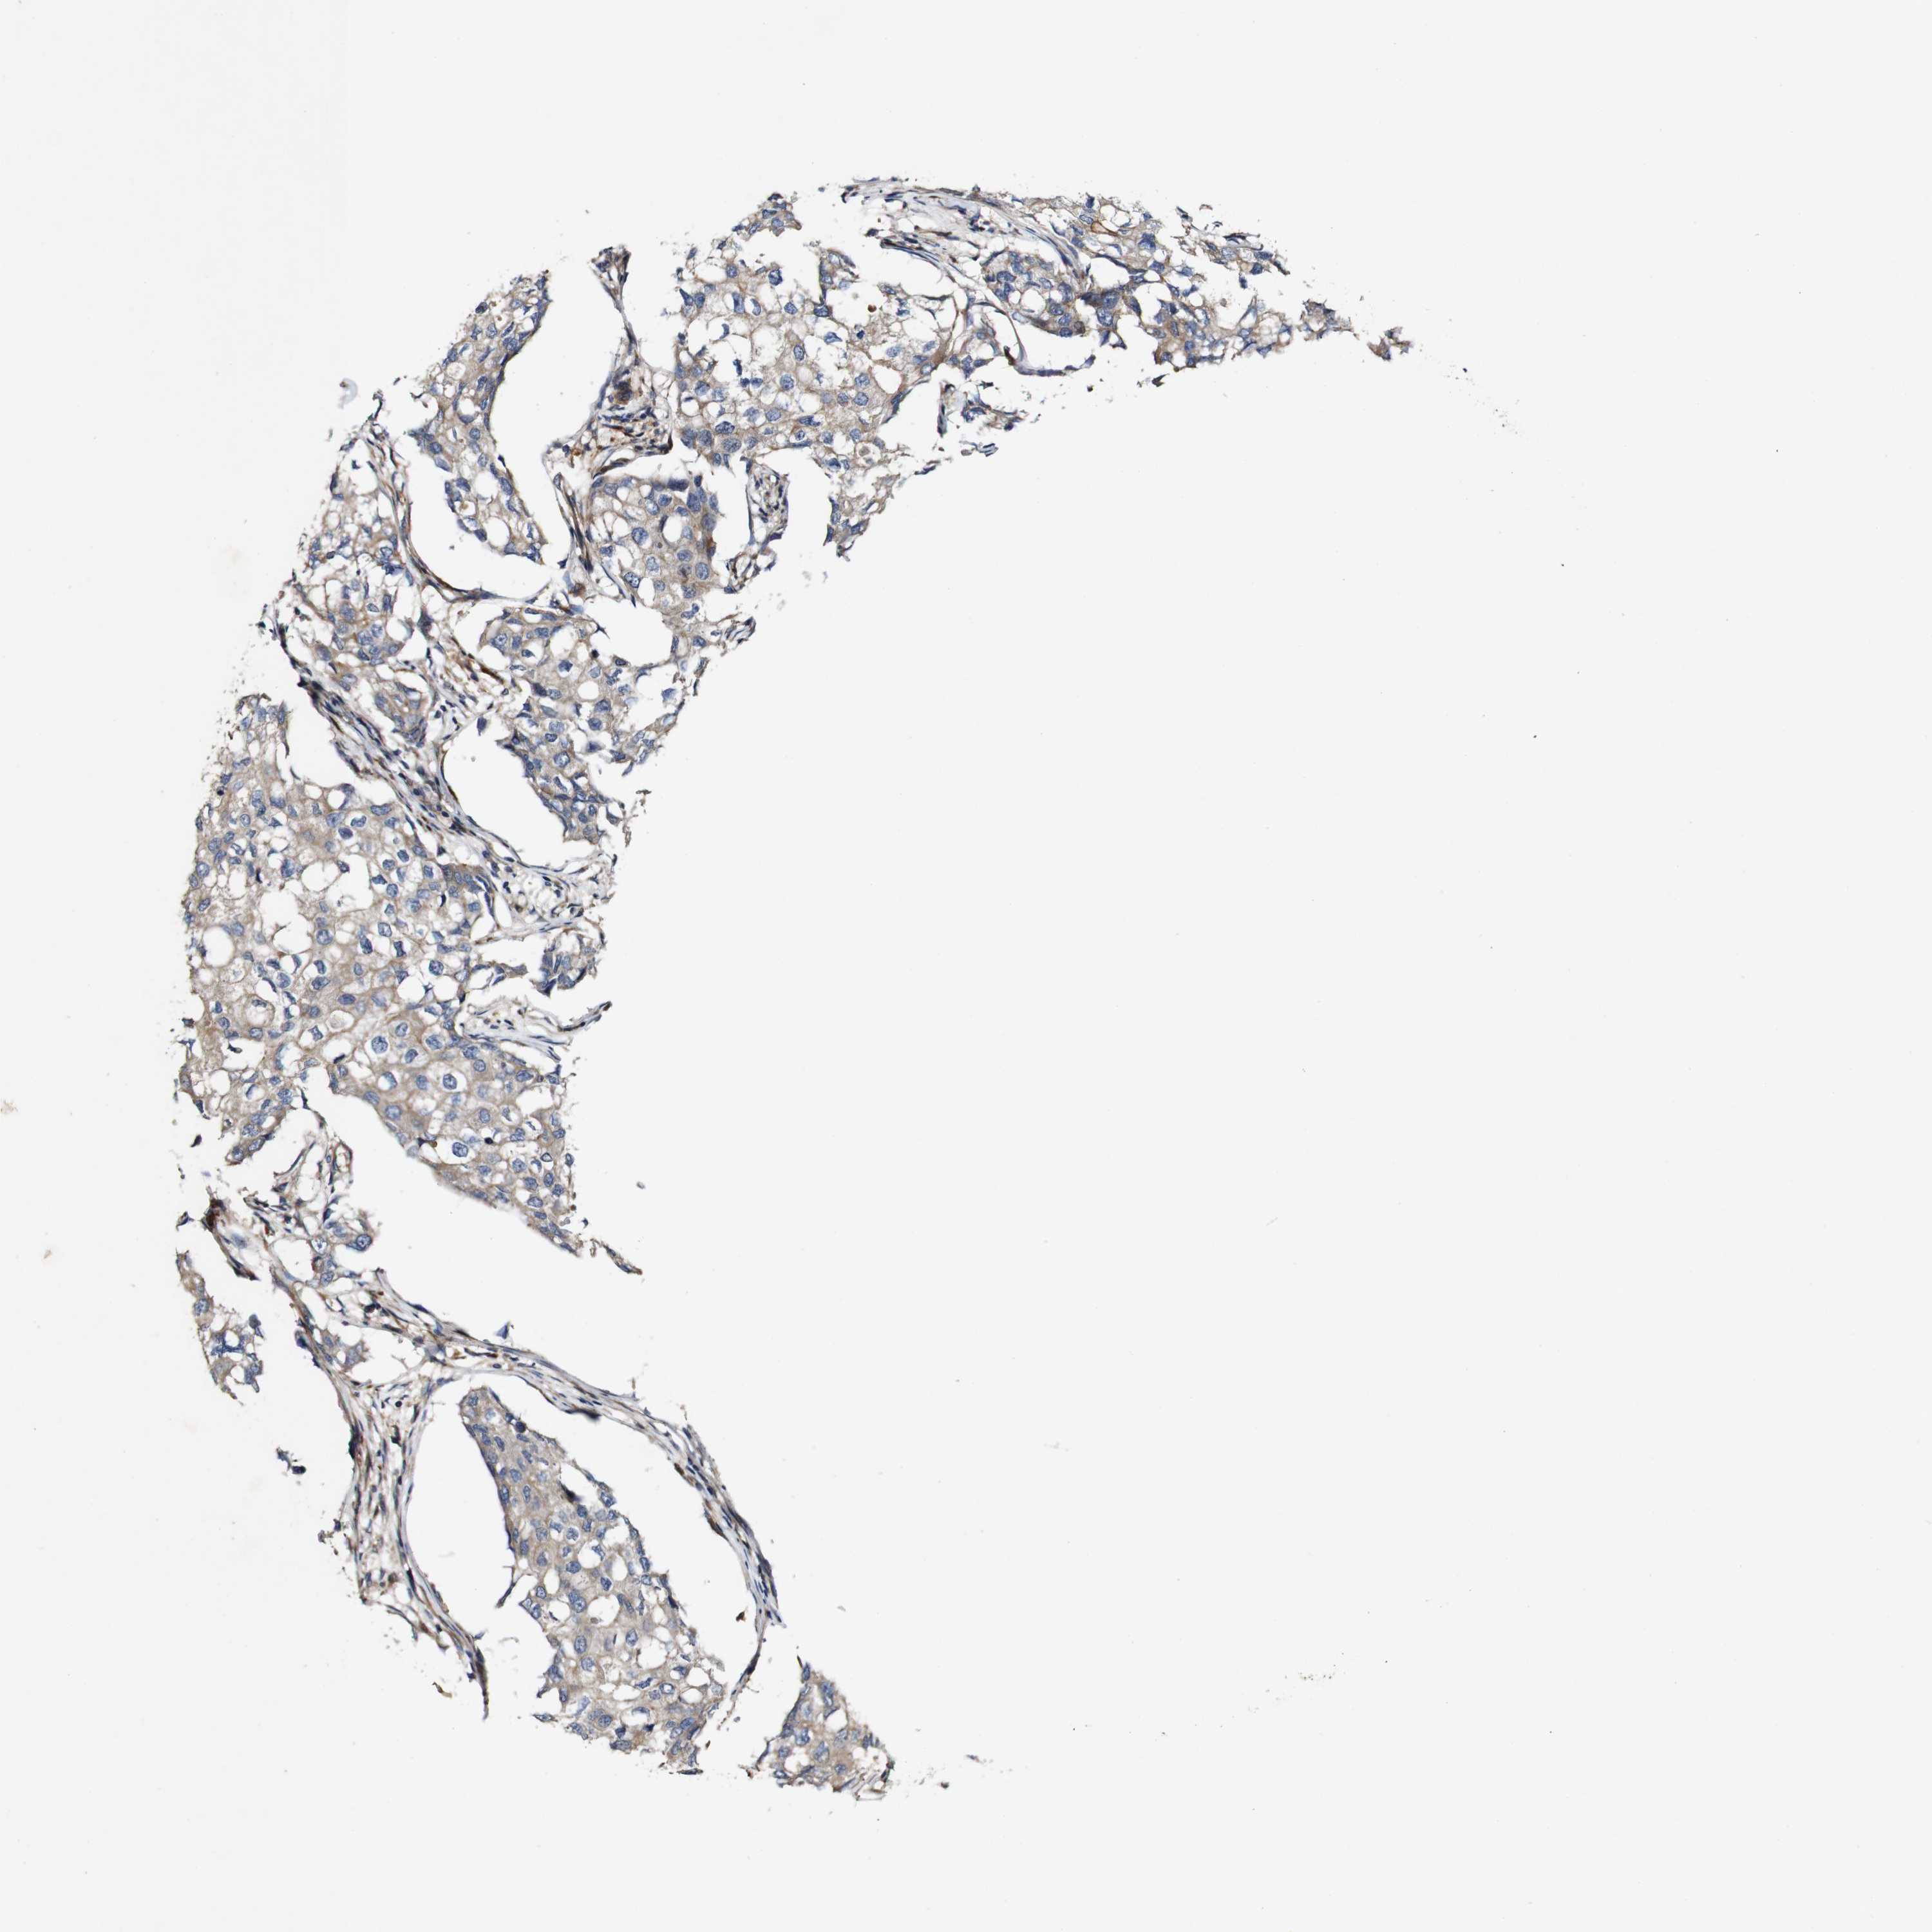

CANCER BREAST CANCER Show tissue menu

BRCA TCGA BRCA VALIDATION PROTEIN EXPRESSION